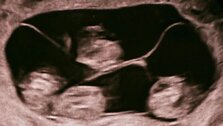

Уникальный случай произошел в Санкт-Петербурге. Там родились четыре близняшки. Они являются однояйцевыми близнецами.

Таких случаев в России еще не описано. Согласно статистике, это один шанс на 15,5 миллиона родов. Девочки появились на свет на 32-й неделе. Операцию провела большая команда врачей: каждую новорожденную сразу принимали неонатологи.